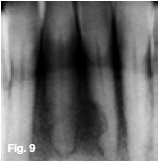

Figures 1, 2, & 3 show a mixed radiolucent/opaque lesion affecting the maxilla, crossing the midline in an edentulous patient, causing flattening of the palate. A lateral skull radiograph of another patient (Fig. 4) shows osteoporosis imperfecta in the posterior and anterior parts of the skull (green arrows) along with thickening of the calvarium and cranial vault which are cardinal radiological signs of the condition. Figures 5 & 6 illustrate "cotton wool" radio-opacities in the skull and the base of the skull shows dense sclerosis. All the images mentioned so far are typical features of Paget's disease. Sir James Paget, surgeon and pathologist who is best remembered for naming Paget's disease. The disease is idiopathic and can be divided into three stages: initial bone resorptive phase, vascular phase with osteoblastic repair, and approximal/ sclerosing phase. The jaws are involved in approximately one in Ave cases, with the maxilla being affected about twice as frequently as the mandible. During the initial phase of bone resorption, the affected bones may be deformed or painful, particularly the weight-bearing structures such as the long bones of the legs (Fig. 7A & B). Later the affected bones expand, commonly in the maxilla, mandible or cranium. At this stage, the dental patient who wears full dentures may complain that the fit of the dentures is becoming progressively poorer. When the maxilla is affected, the alveolar ridge widens and the palatal vault can flatten (Fig. 2). When teeth are present, they may become increasingly spaced, with extensive jaw enlargement. Neurologic complaints can result from increased deposition of bone in the areas of the foramina of the skull causing headaches, auditory disorders progressing to deafness, visual disorders progressing to blindness, facial paresis, and vertigo. The bones are relatively brittle; hence, fractures are likely. Generalised radiolucency/osteoporosis intermediate stage with mixed radiolucency/radiopacity, "driven snow" coarse trabeculation, "cotton wool" radio-opacities in the final stage (Figs. 5 & 6). Hypercementosis, loss of lamina dura, obliteration of the periodontal ligament spaces (Fig. 8) and external root resorption (Fig. 9) may also be present. The upper hand wrist radiograph (Fig.10) of another patient shows the disease affecting the phalanx of the third digit.